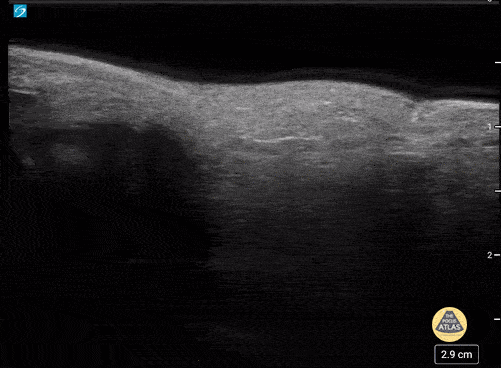

5 yo male with a phalanx fracture of the hand in a water bath before and after reduction. Case series 2 of 2 Contributor: Paul Khalil, MD Nicklaus Children's Hospital @khalil3paul